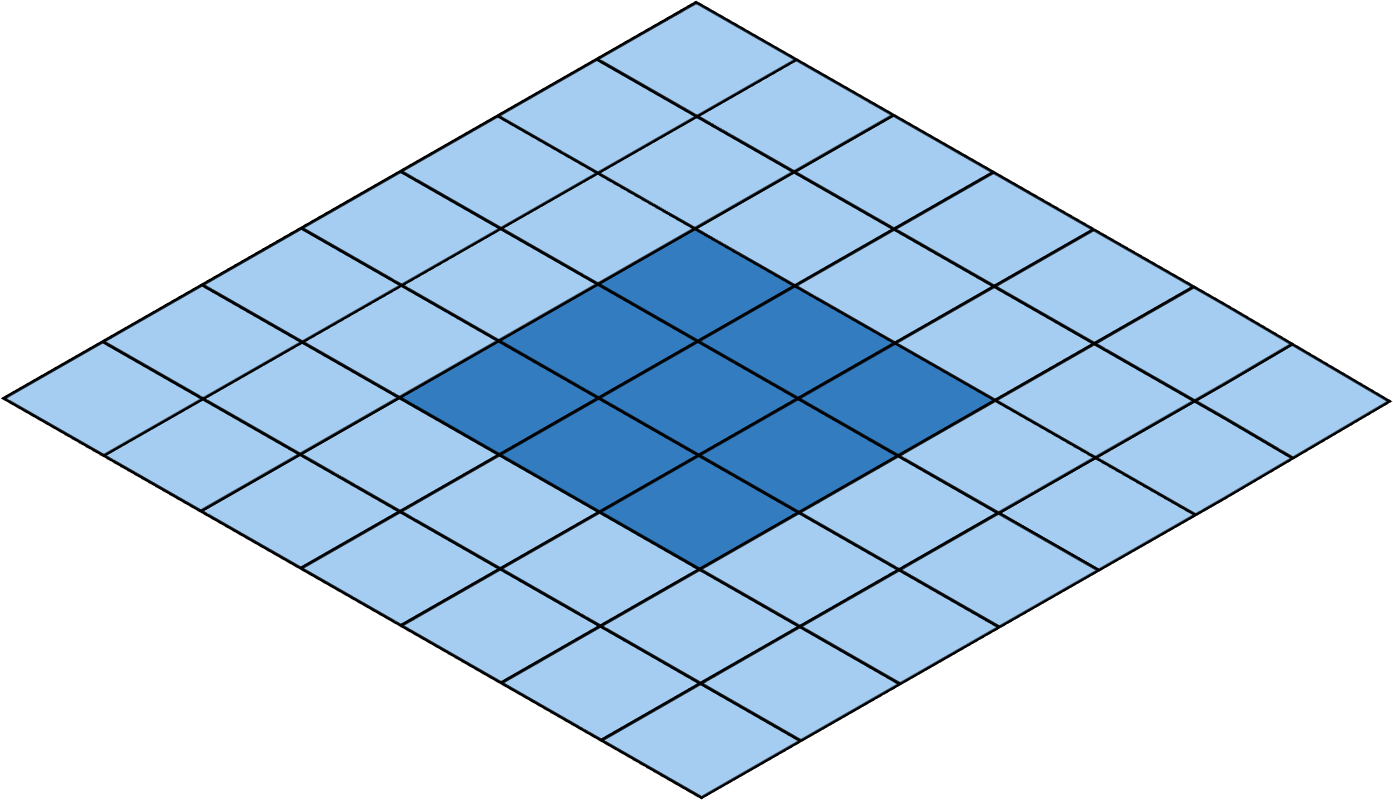

Deep Convolutional Neural Networks (DCNNs) are used extensively in biomedical image segmentation. However, current DCNNs usually use down sampling layers for increasing the receptive field and gaining abstract semantic information. These down sampling layers decrease the spatial dimension of feature maps, which can be detrimental to semantic image segmentation. Atrous convolution is an alternative for the down sampling layer. It increases the receptive field whilst maintains the spatial dimension of feature maps. In this paper, a method for effective atrous rate setting is proposed to achieve the largest and fully-covered receptive field with a minimum number of atrous convolutional layers. Furthermore, different atrous blocks, shortcut connections and normalization methods are explored to select the optimal network structure setting. These lead to a new and full-scale DCNN - Atrous Convolutional Neural Network (ACNN), which incorporates cascaded atrous II-blocks, residual learning and Fine Group Normalization (FGN). Application results of the proposed ACNN to Magnetic Resonance Imaging (MRI) and Computed Tomography (CT) image segmentation demonstrate that the proposed ACNN can achieve comparable segmentation Dice Similarity Coefficients (DSCs) to U-Net, optimized U-Net and hybrid network, but with significantly reduced trainable parameters due to the use of full-scale feature maps and therefore computationally is much more efficient for both the training and inference.